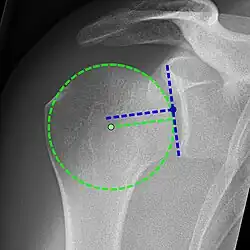

Xray

Projectional radiograph of normal glenohumeral position.[51]

High-riding humeral head in a rotator cuff tear.

X-ray projectional radiography cannot directly reveal tears of the rotator cuff, a 'soft tissue', and consequently, normal X-rays cannot exclude a damaged cuff. However, indirect evidence of pathology may be seen in instances where one or more of the tendons has undergone degenerative calcification (calcific tendinitis). The humeral head may migrate upward (high-riding humeral head) secondary to tears of the infraspinatus, or combined tears of the supraspinatus and infraspinatus.[51] The migration can be measured by the distance between:

• A line crossing the center of a line between the superior and inferior rims of the glenoid articular surface (blue in image).

• The center of a "best-fit" circle positioned over the humeral articular surface (green in image)

Normally, the former is positioned inferiorly to the latter, and a reversal therefore indicates a rotator cuff tear.[51] Prolonged contact between a high-riding humeral head and the acromion above it may lead to X-ray findings of wear on the humeral head and acromion; secondary degenerative arthritis of the glenohumeral joint (the ball and socket joint of the shoulder), called cuff arthropathy, may follow.[50] Incidental X-ray findings of bone spurs at the adjacent acromioclavicular joint may show a bone spur growing from the outer edge of the clavicle downward toward the rotator cuff. Spurs may also be seen on the underside of the acromion, once thought to cause direct fraying of the rotator cuff from contact friction, a concept currently regarded as controversial.